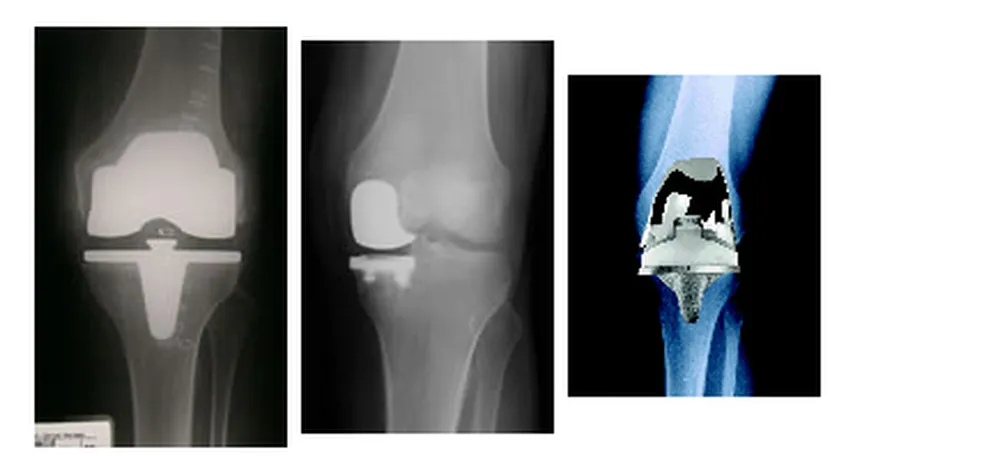

Sind in einem Knie mehr als ein Gelenkabschnitt stark verschlissen, sollten alle Gelenkabschnitte überkront werden. Die zur Stabilisierung des Gelenks wichtigen Bandstrukturen bleiben erhalten. Diese Form des Kniegelenkersatzes nennt man „kompletten“ oder in der Fachsprache „biconylären Oberflächenersatz“. Hierbei handelt es sich um die landläufig gut bekannte Knie-TEP.

Allen oben genannten Möglichkeiten des Gelenkersatzes ist gemeinsam, dass die neuen Gelenkflächen aus Metall (Titan oder Chirurgenstahl) bestehen, zwischen denen eine Gleitfläche aus hochbelastbarem Kunststoff liegt. Die metallenen Gelenkflächen werden in der Regel mit einem Zweikomponenten- Kleber, dem sogenannten Knochenzement, auf den entsprechend vorbereiteten Anteilen des Ober- und Unterschenkelknochens fixiert. Eine zementfreie Verankerung, wie man sie bei der Hüft- oder Schultergelenk-Prothese kennt, ist aufgrund der anatomischen Verhältnisse am Knie die Ausnahme.